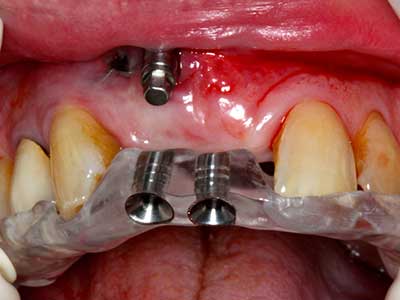

Abb. 23: Finale Mobilisation des palatinal gestielten Distraktionssegmentes mit dem Meissel.

Abb. 24: Anbringen des Distraktors (TRACK-System, KLS Martin).

Abb. 25: OPTG nach Erreichen der finalen Distraktionshöhe, vor Konsolidierungsperiode.

Abb. 26: Nach einer Konsolidierungs-phase von vier Monaten zeigen sich stabile Verhältnisse vor Implantatinsertion.